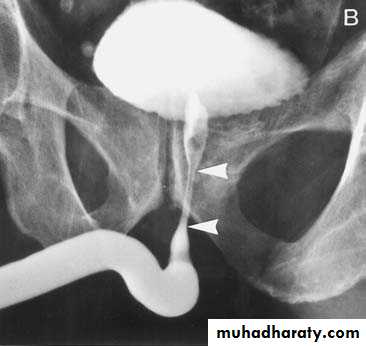

All patients with a suspected urethral injury should undergo a retrograde

urethrogram (RUG)

DX

The diagnosis of posterior urethral injury is suggested by a history of pelvic fracture,

• Triad of pelvic fracture, blood at the meatus and inability to void are diagnostic of urethral injury

RUG

Posterior Urethral Injury

The posterior urethra consists of the prostatic and membranous urethra.

Almost all posterior urethral injuries are caused by pelvic fracture from blunt trauma. Urethral injury occurs in 10% of men with pelvic fractures.

The prostate and bladder are often pushed cephalad by hematoma, resulting in a high-riding prostate on rectal exam " pie in the sky" bladder on cystogram.